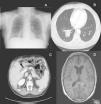

Dos semanas después de la confirmación histológica de las metástasis cutáneas el paciente acudió a Urgencias por un cuadro de tres días de evolución consistente en tos con expectoración blanquecina y dolor en la base de ambos hemitórax. En la radiografía de tórax se apreció una radioopacidad mal delimitada a nivel basal derecho (fig. 3A). Dados los antecedentes del paciente se realizó una TAC que confirmó la presencia de una gran masa de 4,3cm en el lóbulo inferior derecho, así como múltiples nódulos pulmonares y afectación de ganglios mediastínicos (fig. 3B). También se objetivaron metástasis intrahepáticas, perirrenales y adrenales (fig. 3C), subcutáneas y en el tejido muscular. Un mes más tarde acudió de nuevo a Urgencias por un cuadro de desorientación y crisis convulsivas tónico-clónicas generalizadas. En la RM cerebral se objetivó una prominencia del plexo coroideo izquierdo con presencia de una imagen de morfología irregular hipercaptante, compatible con lesión metastásica (fig. 3D). Finalmente, tras un deterioro general progresivo, se produjo el fallecimiento del paciente tan solo 6 semanas después del diagnóstico de las metástasis cutáneas.

A. Radiografía de tórax antero-posterior en la que se aprecia una radioopacidad mal delimitada a nivel basal derecho. B. TAC torácica que muestra una gran masa de 4,3cm en el lóbulo inferior derecho y otros nódulos pulmonares de menor tamaño. C. TAC abdominal que muestra metástasis intrahepáticas, tanto a nivel perirrenal como adrenal derecho. D. RM cerebral de corte axial en la que se aprecia prominencia del plexo coroideo izquierdo con presencia de imagen de morfología irregular hipercaptante, compatible con lesión metastásica.